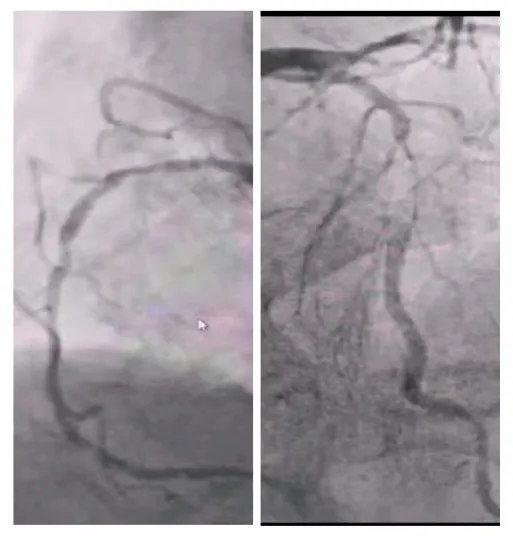

2025年深秋的一个清晨,82岁的马奶奶(化名)因持续胸闷气短被家人送至医院心内科。心脏超声检查显示,她的左心房内有一个直径近5厘米的肿瘤,随心跳规律摆动,如同一个随时可能破裂的“不定时炸弹”。更危急的是,冠脉造影进一步揭示其冠状动脉多支血管严重狭窄,左前降支狭窄达95%,回旋支中段完全闭塞,右冠状动脉弥漫性病变—两种致命性心脏疾病的叠加,让这位高龄患者的生命岌岌可危。

术前冠脉造影